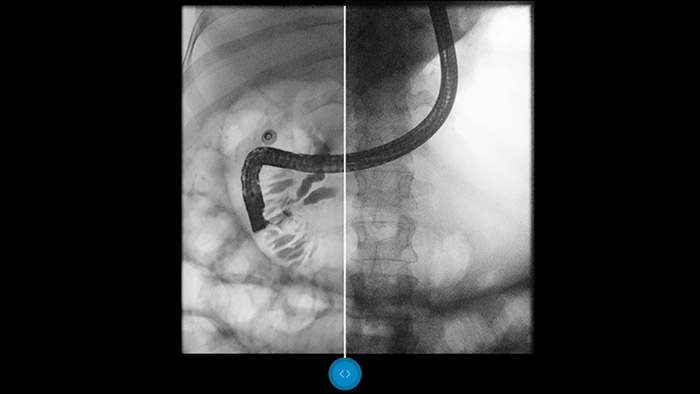

Vergleichen Sie Dynamic UNIQUE mit einer klassischen Bildverarbeitung und lassen Sie sich überzeugen.

Bei den heutigen Durchleuchtungsuntersuchungen sind Niedrigdosis-Einstellungen durchaus üblich. Leider führt dies zu Bildern mit hoher Quantenstreuung, durch die Ihnen eine sichere Diagnose erschwert wird. Die Echtzeit-Bildverarbeitung von Dynamic UNIQUE (Unified Image Quality) ist ein Innovationsvorsprung, von dem Sie nur bei Radiographie-/Fluoroskopiesystemen von Philips, einschließlich dem ProxiDiagnost N90 und dem CombiDiagnost R90, profitieren können. Mit Dynamic UNIQUE optimieren Sie Ihre Bildgebungsergebnisse und somit Ihre Diagnosesicherheit.

Dynamic UNIQUE liefert hervorragende Detailerkennbarkeit mit Echtzeit-Rauschunterdrückung – vom ersten bis zum letzten Bildbereich. Diagnostische Informationen werden für jeden Bildbereich mit großer Klarheit, der richtigen Helligkeit und äußerst niedriger Latenz angezeigt. Die Bilddarstellung ist einheitlich und stabil, selbst wenn sich der Bildinhalt schnell verändert. Dynamic UNIQUE bietet durch seine Detailschärfe schnelle und sichere Niedrigdosis-Untersuchungen, um Ihre Diagnosesicherheit zu steigern.